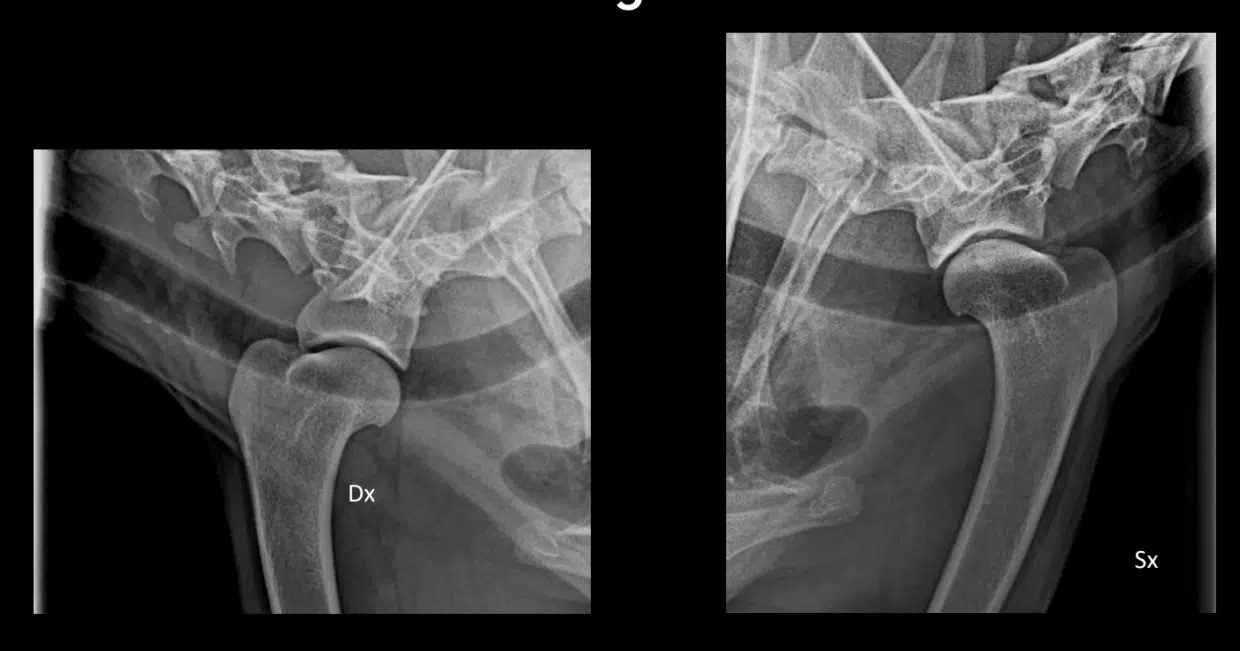

La locomotion est objectivée avec les différents paramètres mesurés à l’aide de l’outil Tendiboots™ Canine. Des examens radiographiques et échographiques ont également été effectués sur Kara.

![]() |